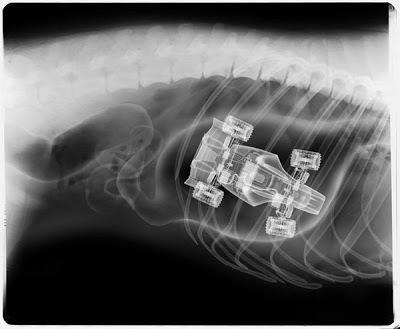

Игрушечная гоночная машинка